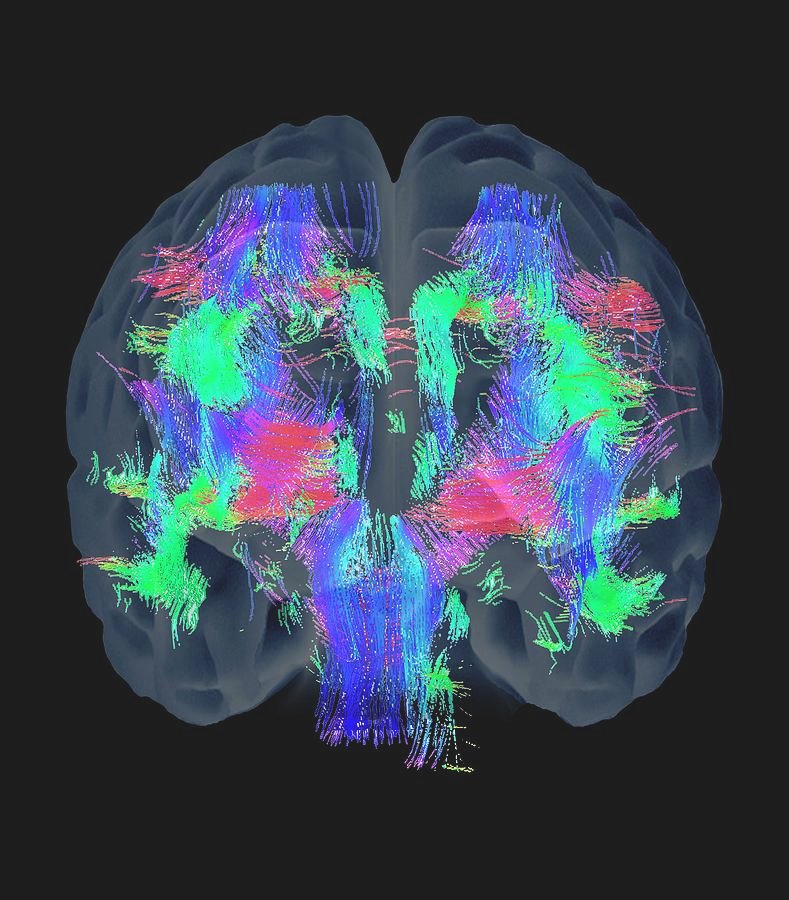

O autismo é um distúrbio neurodesenvolvimental que afeta a comunicação e o comportamento social, apresentando uma ampla gama de sintomas e desafios para aqueles que vivem com a condição. À medida que a pesquisa avança, novas abordagens terapêuticas estão sendo exploradas, e o cannabidiol (CBD) emerge como um candidato intrigante no campo do tratamento para o autismo.

Pesquisas preliminares sugerem que o CBD pode influenciar positivamente alguns dos sintomas associados ao autismo, como a ansiedade, agressividade, hiperatividade e dificuldades sociais. O sistema endocanabinoide, que regula funções neurobiológicas, apresenta alterações em pessoas com autismo, e o CBD parece interagir de maneira benéfica com esse sistema, contribuindo para a melhoria de certos aspectos comportamentais. Acompanhe o artigo a seguir para entender um pouco mais:

O sistema endocanabinoide desempenha um papel vital na regulação de diversas funções fisiológicas, como sono, apetite, humor, resposta imunológica e dor. O CBD atua principalmente interagindo com os receptores do sistema endocanabinoide, especialmente os receptores CB1 e CB2. Essa interação pode modular a liberação de neurotransmissores e influenciar várias vias bioquímicas.

O CBD interage primariamente com o sistema endocanabinoide, uma intrincada rede de receptores no corpo humano que desempenha um papel crucial na regulação de diversas funções fisiológicas. Este sistema está envolvido em processos como sono, apetite, humor, resposta imunológica e dor. Devido à sua influência em diversas vias bioquímicas, o CBD pode proporcionar efeitos benéficos para algumas pessoas com autismo.